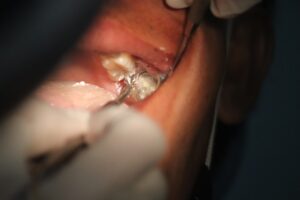

Stomatologia

Procedury stomatologiczne należą do najczęściej finansowanych zabiegów na raty. Wysokie koszty leczenia protetycznego, implantologii czy ortodoncji skłaniają pacjentów do korzystania z elastycznych form płatności. Wprowadzenie systemów ratalnych w gabinetach stomatologicznych znacząco poprawiło dostępność leczenia.